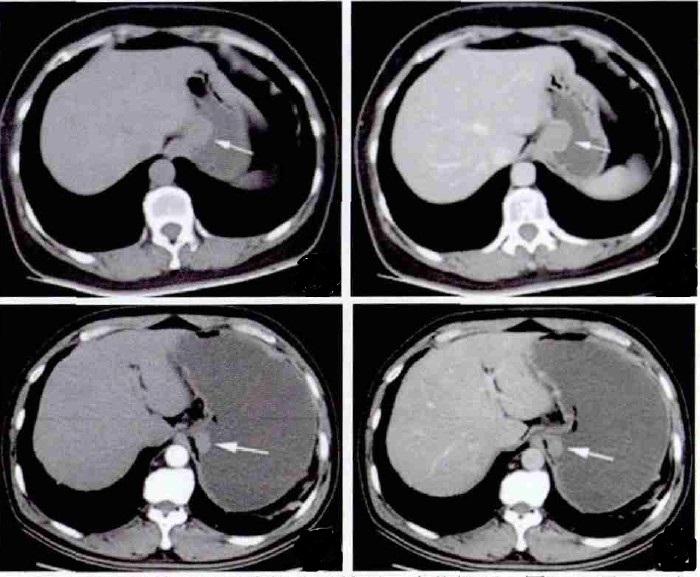

上图可看到胃窦小弯侧软组织密度结节,大小约18mm×17mm,平扫CT值约37HU,增强扫描动脉期可以明显强化,CT值约134HU,门脉期持续呈高强化,延迟期强化减低。余黏膜面未见异常强化,浆膜面光整。胃周未见明显肿大淋巴结。

患者影像学特点

胃窦小弯侧结节状实性占位;

动脉期明显强化,门脉期持续强化,延迟期强化减低,门脉期达到强化峰值;

动脉期病变斑片状强化,门脉期强化范围逐渐增宽;

黏膜面未见异常强化,浆膜面光整。